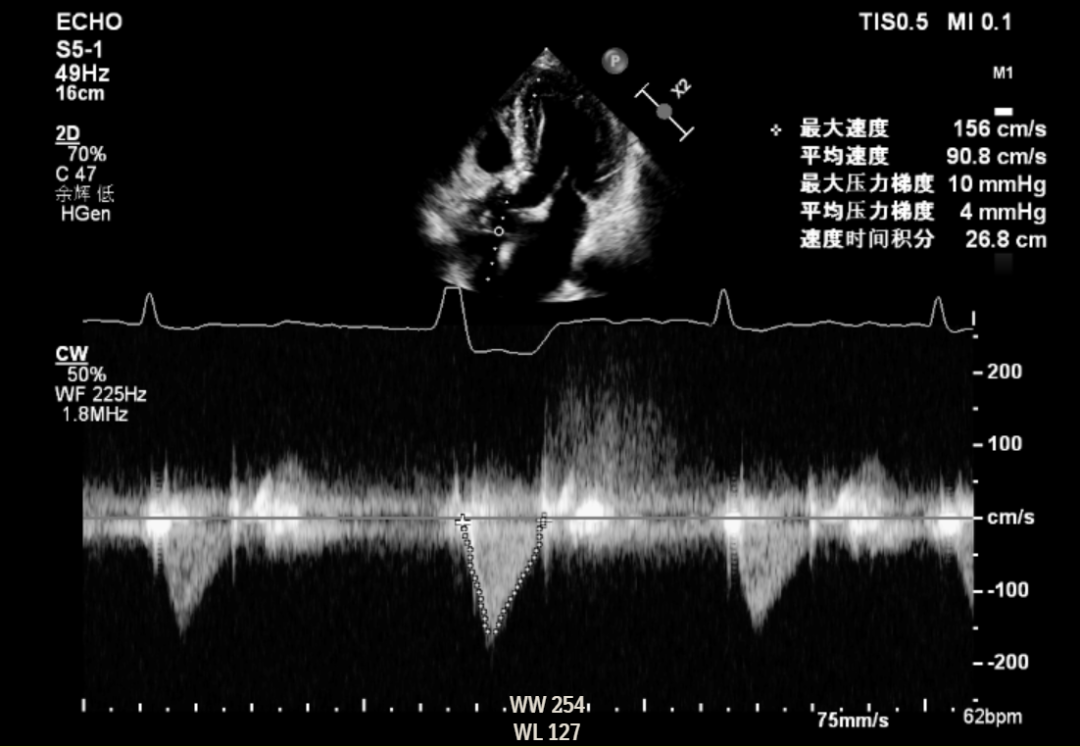

2022年7月6日,葛均波院士及其团队的周达新主任医师、潘文志主任医师、郭克芳副主任医师以及张晓春、张源、陈莎莎、李伟等医师,成功完成世界首例聚合物瓣膜(SIKELIA™)经导管主动脉瓣置换术。该例为80岁男性患者,主要症状为反复活动后胸闷气促,诊断重度主动脉瓣狭窄、心房颤动、高血压。TAVR术程顺利,导管操作时间(skin to skin)27分钟,器械操作顺畅。术后造影显示,瓣膜工作状态良好,跨瓣压差正常,瓣周漏微量。冠脉无阻塞,无传导阻滞。术后即刻拔除气管插管,顺利苏醒。术后六天复查心超提示人工瓣架固定,开放不受限,峰值压差8mmHg,平均压差4mmHg,轻微主动脉瓣反流。患者恢复良好,氨基末端利钠肽前体由术前5688pg/ml下降至1035pg/ml,NYHA 心功能分级由III级改善至II级。术后30天、3个月、8个月随访发现主动脉瓣无明显跨瓣压差,仅微量反流。

术前跨瓣压差

8个月随访情况